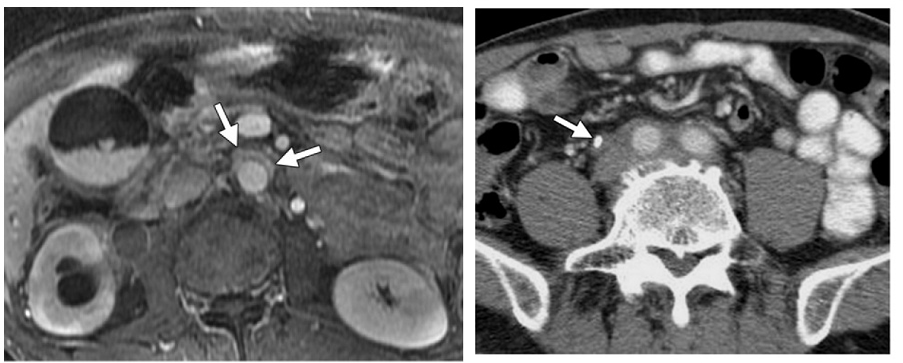

腹膜后纤维化

59 岁男性,增强 T1 显示腹主动脉前方软组织增厚,增强后病灶轻度强化。右侧肾盂及上段输尿管积水扩张,CT 增强显示双侧髂总动脉周围不规则软组织应包绕血管,右侧输尿管支架植入